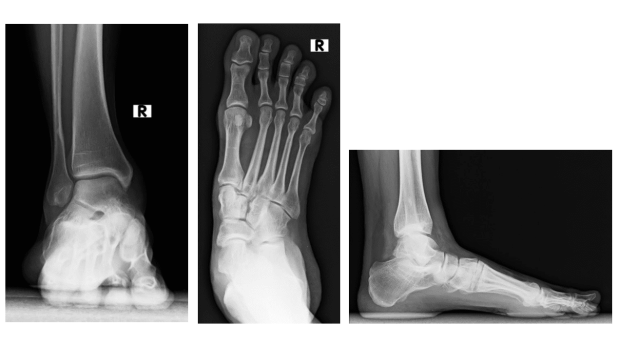

Bei einer 39-jährigen Physiotherapeutin ist seit der Kindheit ein Knick-Senkfuss bekannt. Trotz konsequentem Tragen orthopädischer Schuheinlagen leidet sie unter zunehmenden Beschwerden an der Innenseite des rechten Rückfusses.

Bei einem Knick-Senkfuss weicht der Rückfuss nach aussen ab, während sich das Längsgewölbe abflacht. Dadurch kommt es zur Überlastung der Innenbänder sowie der, für den Erhalt des Längsgewölbes wichtigen, «Tibialis posterior»-Sehne. Ab einem bestimmten Grad der Deformität kann es zu den von der Patientin geschilderten Beschwerden am innenseitigen Rückfuss kommen.

Rechts: Abweichung des Fusses zur Aussenseite.

In der klinischen Untersuchung zeigten sich die Rückfussgelenke noch gut beweglich und die Deformität somit redressierbar, das heisst der Fuss konnte durch manuellen Druck in eine korrekte Form übergeführt werden. Bei der Untersuchung fiel allerdings - wie häufig anzutreffen - zusätzlich eine Verkürzung der Wadenmuskulatur auf, welche über den Zug der Achillessehne am Fersenbein den Rückfuss zur Seite hin abweichen lässt.